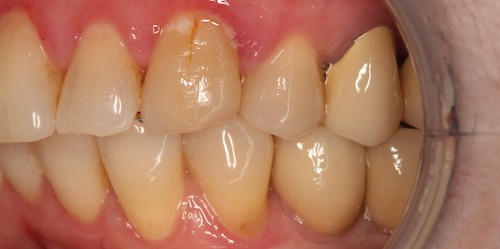

После